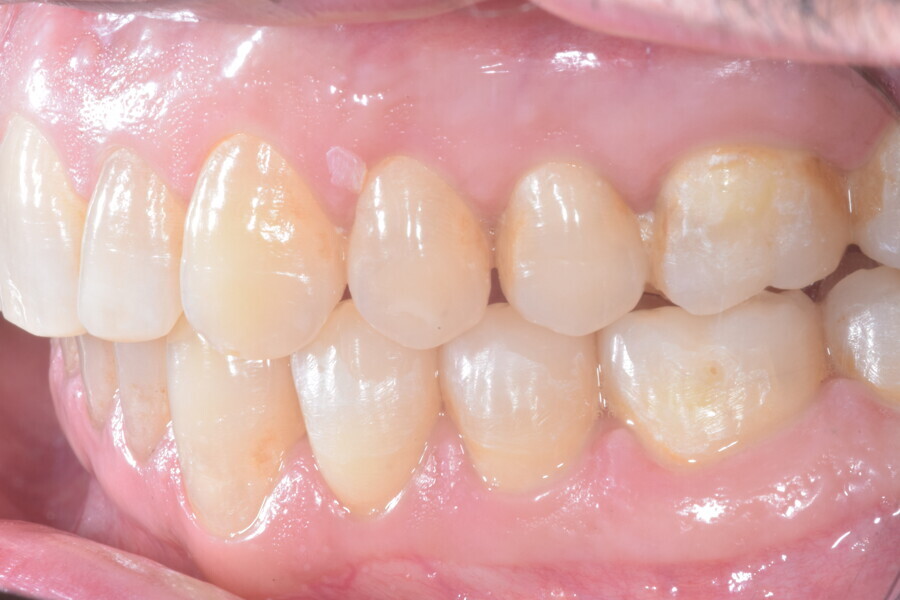

Le plan de traitement numérique (ClinCheck) avait prévu douze aligneurs pour l’arcade maxillaire et dix-sept pour l’arcade mandibulaire. Les objectifs du traitement visaient à combiner les mouvements verticaux d’extrusion des dents postérieures et les mouvements d’intrusion des dents antérieurs, au moyen de rampes d’occlusion, tout en utilisant des taquets d’extrusion pour assurer la désocclusion des dents postérieures et l’intrusion des dents antérieures inférieures, nécessaires au nivellement de l’arcade mandibulaire. La courbe de Spee a été nivelée et le profil plat ainsi que la position des lèvres ont été améliorés par une vestibulo-version des incisives supérieures et inférieures. Le plan avait prévu des élastiques de classe II pour faciliter la vestibulo-version des dents inférieures et les puissants contacts occlusaux postérieurs, avec une extrusion relative des dents postérieures. Une morphologie plus large de l’arcade et une intercuspidation idéale ont été obtenues par des mouvements de torque proches de 0° des dents latérales et postérieures supérieures. Aucune conception technique excessive n’avait été prévue dans le plan de traitement numérique. En raison de l’âge du patient, les aligneurs ont été changés tous les dix jours, dans le cadre d’un traitement d’une durée inférieure à six mois. À la fin de la première série d’aligneurs (Figs. 20–24), un nouveau plan de traitement numérique comportant cinq autres aligneurs a été conçu, en vue d’améliorer l’intercuspidation des molaires sans élastiques. La durée totale du traitement a donc été prolongée jusqu’à 7,5 mois puisque les aligneurs supplémentaires étaient changés toutes les semaines.

À la fin du traitement, on pouvait observer une relation de classe I des canines et des molaires, une légère augmentation de l’inclinaison des incisives supérieures (Ui-FH = 112°), une correction complète de l’inclinaison des incisives inférieures (IMPA = 97,09°) grâce à la vestibulo-version, et une légère amélioration de l’hypodivergence (SN-GoGn = 27°) résultant de l’extrusion relative des dents postérieures, et de l’utilisation d’élastiques de classe II — petite variation (1°) très intéressante compte tenu de l’âge du patient (Figs. 25–35). La ligne du sourire était harmonieuse et correspondait à une relation idéale entre les incisives supérieures et la lèvre inférieure. Le sourire avait été élargi grâce au contrôle du torque des segments latéraux et postérieurs.